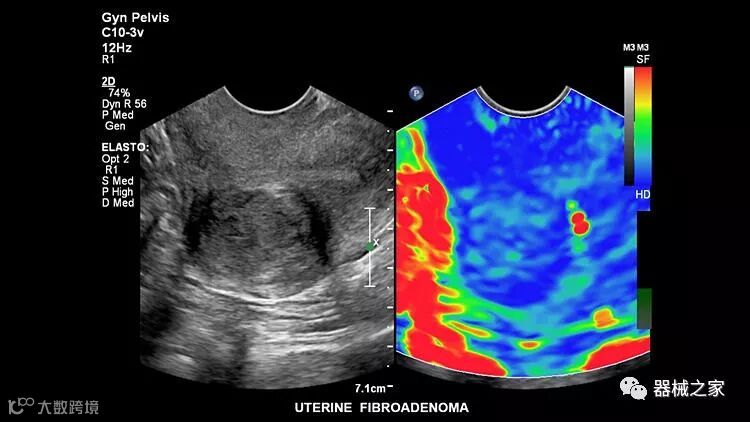

在几年前,超声波无法对小型慢流血管中的血流进行成像,但现在有少数供应商提供具有此功能的系统。该特征提供了另外一种检查病变以指示癌症或炎症的方法。其中一个是佳能Aplio 900 CV系统,它可以显示毛细血管中的血流量。日立的Arietta 65中程系统提供了一种可视化小血管的功能,可以更好地观察肾脏等器官的灌注情况。三星RS85还提供MV-Flow可视化慢流微血管结构。